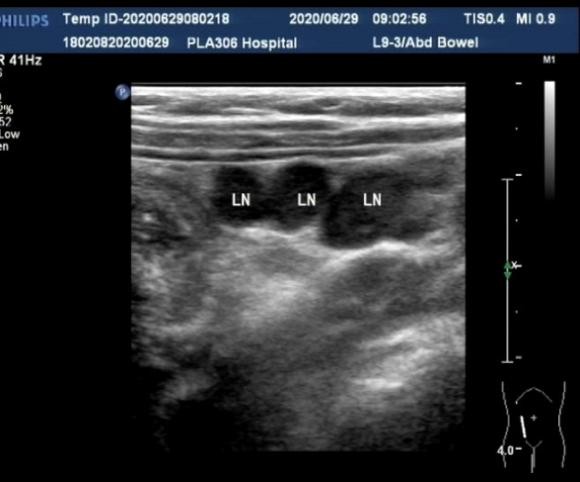

超声表现:腹部可探及包块,横断面呈多层"同心圆"征(图3),纵断面呈多层肠管平行排列的"套筒"征(图4),超声多普勒检查提示包块内血流信号呈点状散在分布(图5);或观察到动静脉频谱,提示肠管受压的症状轻,循环良好,包块内未显示血流信号或血流信号稀少,提示肠管可能存在缺血坏死的症状。部分患儿包块及周围肠系膜内可探及增大的淋巴结(图6)。

图6. 肠套叠周围肠系膜肿大淋巴结图像